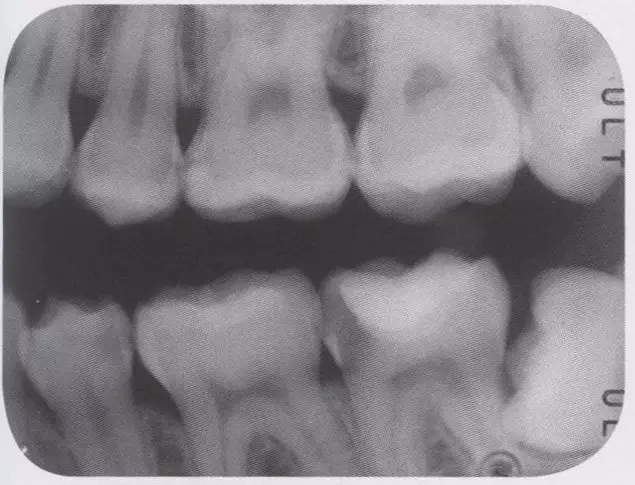

圖2 右5進(jìn)行了全瓷嵌體修復(fù),為了使受力均勻,線角需要呈圓弧狀。

圖3 全瓷嵌體的修復(fù)(右56)。鄰接面產(chǎn)生齲齒的情況(上段,中段左),去除齲齒,并佩戴嵌體(下端)。